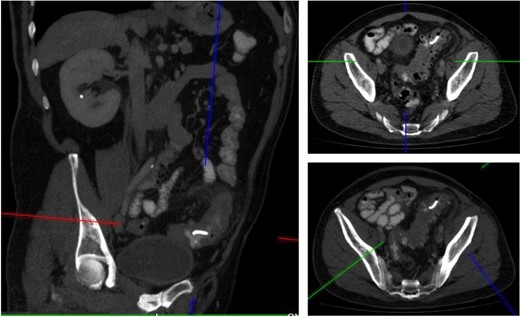

A 52-year male was referred to the surgical team for a 1-day history of left iliac fossa pain accompanied by nausea and the inability to open his bowels for 48 hours. The pain was 9/10 in severity, sharp, persistent and with a gradual worsening onset. The patient was previously diagnosed with extensive diverticular disease and admitted 2 months prior with acute sigmoid diverticulitis. 18 months earlier he underwent an emergent laparoscopy for an unclear pelvic inflammatory mass on CT, that suggested either severe sigmoid diverticulitis or appendicitis. He also had multiple polyps throughout the colon, that were endoscopically removed. The patients past medical history was significant for a non-flow limiting coronary artery disease, arterial hypertension and an allergy to penicillin and tetracycline. Temperature on admission was 38.7 C, blood pressure of 149/109 mm/Hg, pulse of 109 bpm and a respiratory rate of 20/min with O2-saturations of 96% on room air. The abdomen was soft with tenderness and guarding over the left iliac fossa. Bowel sounds were present. Investigations showed a white cell count of 17.6 tsd/ul and a CRP of 64 mg/l. No pneumoperitoneum was detected on an erect chest x-ray. Treatment with ciprofloxacin and metronidazole was started and the patient kept nil per mouth. CT imaging showed extensive sigmoid diverticular disease with marked pericolonic fat stranding and free gas tracking into the mesenteric fat. Gentamycin was added and within 3 days the patient’s clinical symptoms improved. He was apyrexic and the white cell count dropped to 10.9 tsd/ul. A repeat CT scan showed a stable appearing localized perforation with reduced free gas and no signs of collection. However, of note was a small curvilinear metallic foreign body within the lumen of the sigmoid colon of uncertain etiology (Fig. 1). On questioning, the patient recalled a mechanical fall with a head contusion 9 days prior to admission during which he lost his partial denture. The patient was commenced on laxatives and despite bowel movement on the following day, the foreign body did not pass. A PFA showed the persistent presence of the metallic foreign body over the sigmoid colon, which raised the suspicion of impaction (Fig. 2). The patient was prepared for colonoscopy and the foreign body was identified impacting the lumen of the sigmoid colon (Fig. 3). However, endoscopic retrieval failed and the decision was made to proceed with laparoscopic anterior resection. Intraoperative findings showed a rigid and thickened sigmoid colon with adhesions and a diverticular abscess. About 22 cm of sigmoid colon was resected and the procedure was completed with a primary colo-rectal end to end anastomosis, using a 31 mm CEEA-Stapler. The resected sigmoid colon contained the lost partial denture, which showed impaction and perforation into the sigmoid mesocolon (Fig. 4). Following surgery, the patient was transferred to the surgical ICU for 24 h observation and discharged home after one week.

PFA showed the persistent presence of a metallic foreign body over the sigmoid colon.